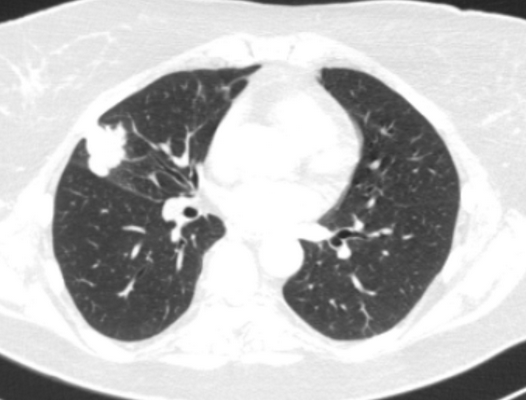

- по объему резекции (лобэктомии (удаление доли легкого), билобэктомии (удаление двух долей легкого), пневмонэктомии (удаление целого легкого)),

Фото 3 — Лобэктомия

Фото 4 — Пневмонэктомия

При лечении местнораспространенного злокачественного образования с переходом на главный бронх и лёгочную артерию, в тех случаях, где раньше единственным вариантом оперативного лечения являлась пневмонэктомия, сейчас возможно выполнение органосохранных операций. В этом случае иссекается пораженный участок главного бронха с последующим восстановлением непрерывности (бронхопластические и ангиопластические лобэктомии)

Фото 5 — Схема верхней бронхопластической лобэктомии